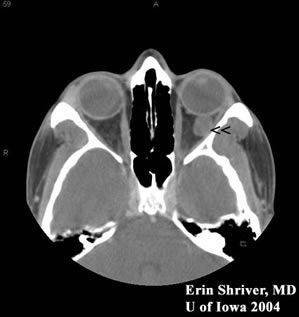

Figure 5. CT scan of orbits notable for a well-circumscribed, intraconal, round mass that was not eroding into surrounding tissues or bone. Mass was isodense to muscle (arrow heads).

CT CT

• CT scan shows well-circumscribed, intraconal, round mass without invasion into adjacent soft tissue and bone.